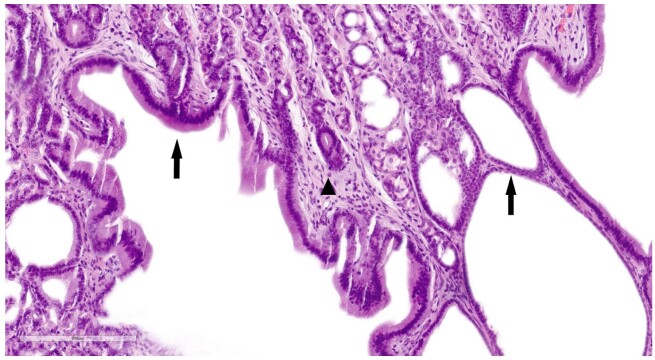

Ménétrier's disease is a rare human condition that causes diffuse hypertrophy of the gastric rugal folds. A similar condition in dogs has been reported as Ménétrier-like disease (MLD). To date, only two feline cases have been reported, and treatment was either unsuccessful or not documented. A 3-year-old female spayed Devon Rex cat was presented with acute nausea, retching, and vomiting. Within two months, multiple tests were performed to reach the diagnosis. Macroscopically, during gastroduodenoscopy, cerebriform hypertrophic gastric mucosal folds were observed in the gastric fundus, cardia, and greater curvature of the stomach. Superficial biopsy sampling of the gastric mucosa showed mild mucosal oedema and low numbers of Helicobacter spp. Considering the course of the disease, persistent gastrointestinal symptoms, and quality of life, a partial gastrectomy was performed. Histology of full-thickness biopsies confirmed hyperplastic fibrosing gastropathy with multifocal cystic dilated gastric glands resembling Ménétrier-like disease in dogs. At the time of the 3-month follow-up, the cat was asymptomatic, and the gastroduodenoscopy was unremarkable. This case report presents clinical findings, challenging diagnostics, and a novel treatment option in a cat with hyperplastic fibrosing gastropathy. To the authors'knowledge, this is the first reported successful surgical management of MLD in a cat.